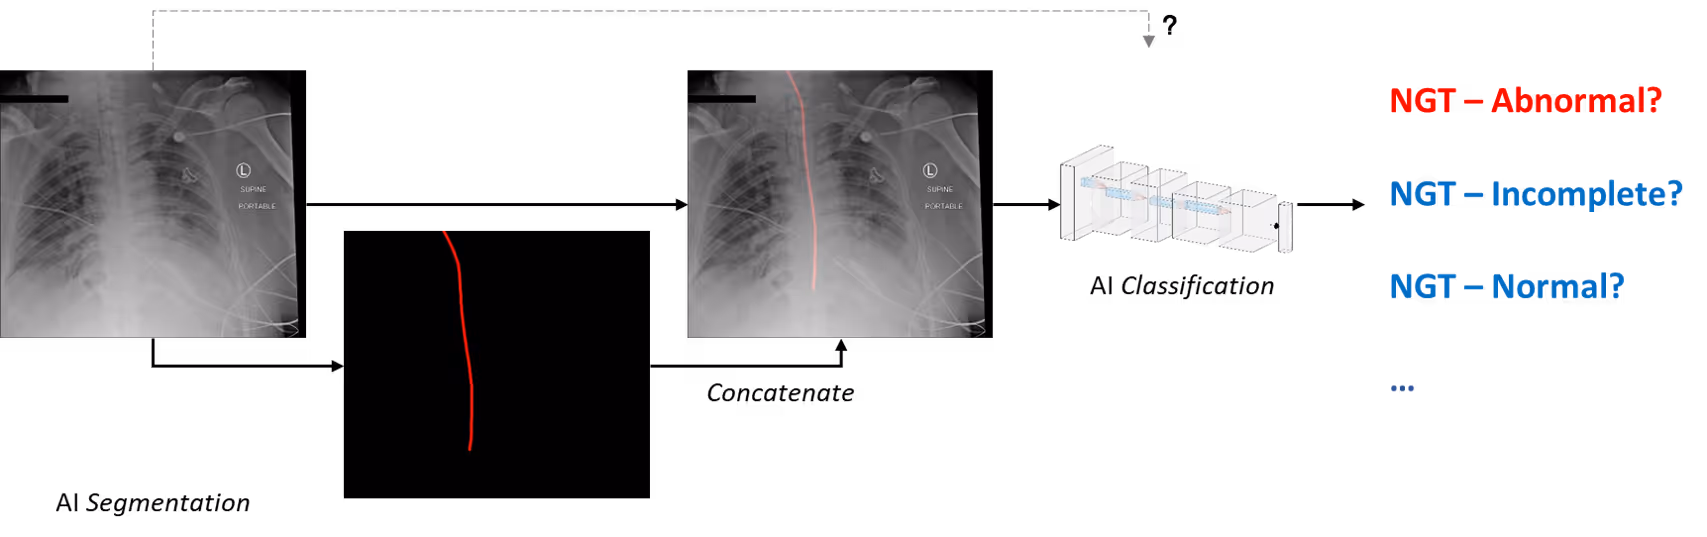

We incorporated artificial intelligence(AI) elements into the games by embedding a deep learning model trained and validated for NGT detection and classification. The tube is segmented and then classified into abnormal, indeterminate (incomplete), or normal.